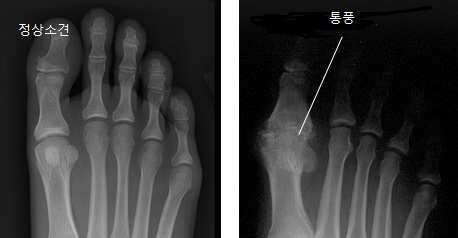

무지외반증(Hallux valgus)

이는 무지가 제1중족지 관절에서 외측을 향하여 경사져 외반되어 있고, 제1중족골은 제2중족골과 멀어지도록 내측으로 기울어 져 있게 되며, 흔히 제1중족골 두부의 내측 비대가 동반되는 병변이다. 그리고 제1중족골 두부의 내측이 비대된 부위에 흔힌 점 액낭(bursa) 이 형성되어 있는데 이를 건막류(bunion) 라 부른다.